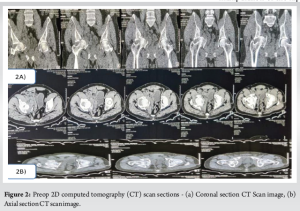

Xray (Fig. 1) and computed tomography (CT) scan (Figs. 2 and 3) were done to find out that he had an isolated Quadrilateral plate fracture with intrapelvic dislocation of the head femur with a napkin ring constriction around the dislocated head femur. However, both the anterior and posterior acetabulum columns were intact.

Owing to the neglected and complex nature of the fracture along with incarcerated head femur we counseled the patient about the prognosis associated with the possible treatment options – Open reduction and internal fixation (ORIF) of the quadrilateral plate and THA with medial wall reconstruction. Initially, we planned for ORIF with Quadilateral plate fixation for which we had positioned him supine. Closed reduction was first attempted using lateral traction by a Schanz pin inserted in Greater trochanter along with longitudinal traction and closed manipulation of the hip. As anticipated, the closed reduction maneuvers were unsuccessful, following which we used the anterior intrapelvic approach to reduce the quadrilateral plate. Hereby the acetabular columns were found to be intact with a comminuted quadrilateral plate fracture. Furthermore, the fractured quadrilateral plate was osteopenic and friable owing to the delayed presentation. There was a napkin ring constriction and dense fibrosis around the head femur. The fibrosis was cleared and using ball spike it was tried to reduce the head femur back into the acetabular cavity, but due to the napkin ring constriction, it wasn’t possible to reduce the head femur despite the best reduction maneuvers and traction. Furthermore, the fractured quadrilateral plate was too osteopenic for a robust buttress fixation. The only option left for reduction was to do a double anterior column osteotomy or proceed for primary THA. Keeping in mind, the age of the patient, long-standing nature of the dislocated head femur, necrotic patch in the superomedial aspect of the head femur along with the incarcerated head, osteopenic quadrilateral plate it was decided to proceed with THA. Subsequently the patient was positioned in lateral decubitus position for THA. The hip joint was exposed using standard posterior approach. In situ napkin osteotomy of the neck femur done and the head femur was taken out piecemeal using a corkscrew, blunt hohmann retractors and bone nibbler with utmost care of not causing any inadvertent injury to the acetabular fossa. Once the entire head was taken out as further confirmed by C-arm, acetabular reaming was done in the peripheral rim to obtain a good viable host bone interface for using an uncemented cup. Now we had a Paprosky type 2C defect (medial defect to deal with for which we used a titanium mesh secured to the medial defect after appropriate contouring over which morselized autograft (obtained from extracted head femur) was placed. Reverse reaming of the acetabular floor was done to get an evenly distributed graft over the cavity and uncemented acetabular cup size 52 was used to obtain a line-to-line fit which was further augmented with 3 acetabular screws in the iliac buttress. A stable acetabular component insertion was thus obtained with the quadrilateral plate left untouched. The Highly crosslinked Polyethylene liner was next inserted into the acetabular cup and thereafter femoral preparation was done using the standard technique – uncemented Hydroxyapatite-coated Femur stem size 4 was thereby used for femoral component with head size 32. The prosthetic hip was reduced and adequate stability with a good range of motion without impingement was confirmed. The patient was mobilized from postoperative day 2 and allowed toe touch weight bearing gradually progressing to partial weight bearing and then to full weight bearing by 3 weeks. There was no limb length discrepancy and the patient was able to do straight leg raise and abduction against gravity by 6 weeks. Radiographs revealed well incorporation of the bone graft with no evidence of loosening (Fig. 4). He could return to his daily activities at 6-month follow-up with mHHS of 91 after year (Fig. 5). The patient did not have any complications such as infection. Heterotopic ossification or dislocation.